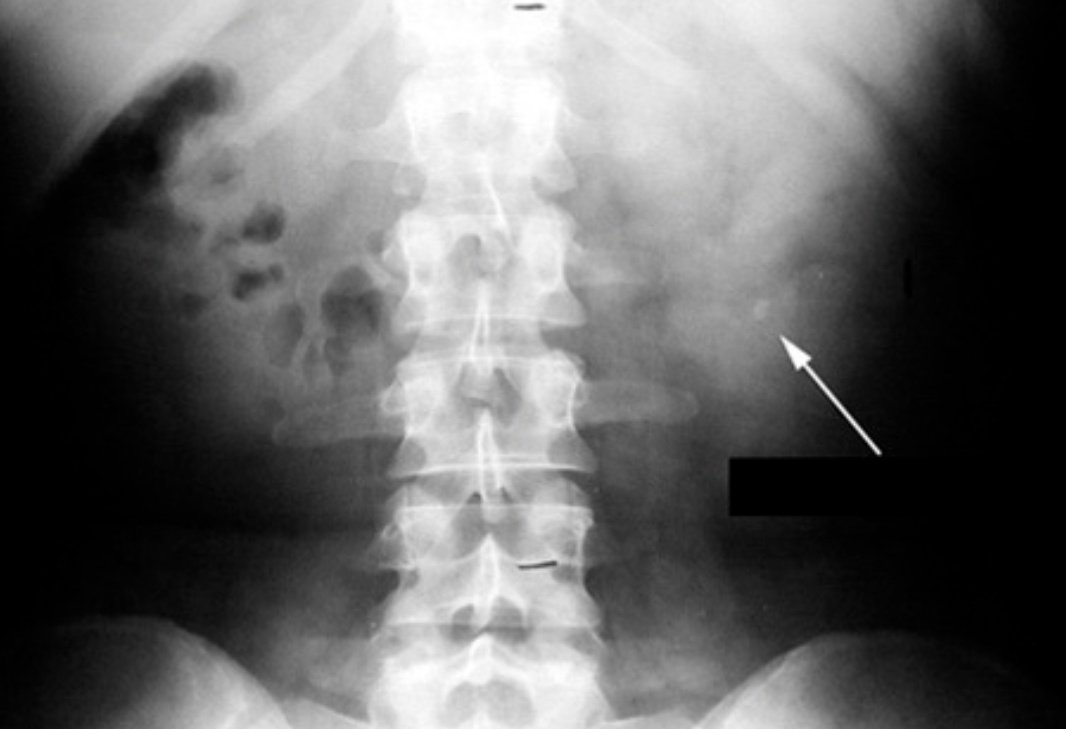

2️⃣لا يوجد تشخيص طبي اسمه( عندك املاح) كل انسان لديه نسبة من الاملاح والمعادن في الدم لها توازن مهم وليست تشخيص يظهر بالاشعه ..

اما توجد حصوات او لا توجد

عدم توازن الاملاح بالجسم له مؤشرات مختلفه وليست بالضروره مرتبطه بتكوين الحصوات ولا تظهر بالاشعه..